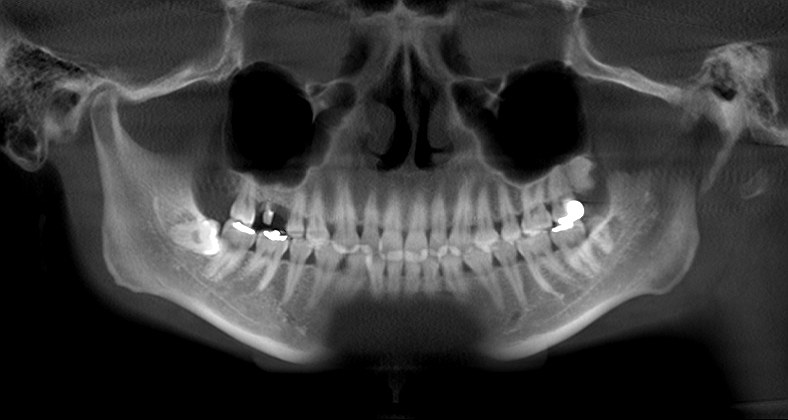

術前のパノラマになります

術後のパノラマになります